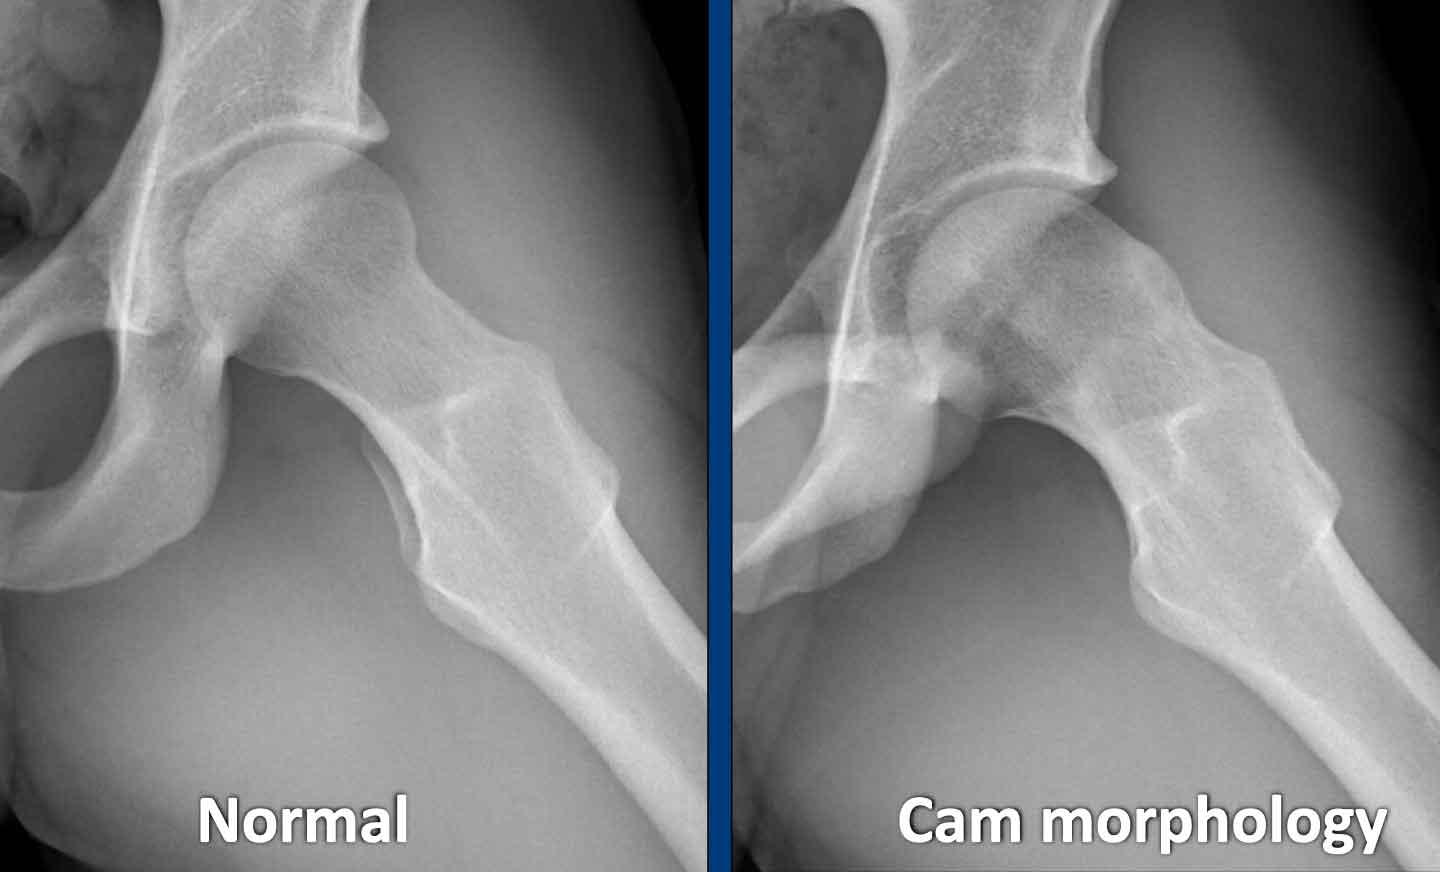

Cam morphology

Hình thái Cam đề cập đến một phần lồi xương lành tính phát triển tại chỗ nối chỏm-cổ xương đùi của khớp háng, thường kết hợp với tình trạng mất hình cầu của chỏm xương đùi.

Hình thái này phát triển trong giai đoạn thanh thiếu niên và không xuất hiện sau khi đầu xương đùi đã trưởng thành. Nó gây ra tình trạng chỏm và cổ xương đùi va chạm vào ổ cối, dẫn đến tổn thương sụn viền và sụn khớp, có thể gây đau khớp háng, đặc biệt khi thực hiện các hoạt động liên quan đến xoay hoặc gấp khớp háng.

Có nhiều tuyên bố đồng thuận quốc tế khuyến nghị sử dụng thuật ngữ hình thái Cam. Các thuật ngữ như tổn thương Cam, lồi xương, hoặc biến dạng báng súng nên được tránh sử dụng, vì hình thái này cũng có thể xuất hiện ở nhiều vận động viên không có triệu chứng.

Khi quan sát thấy một phần lồi xương hoặc độ lồi xương, như được minh họa trong hình, có thể gọi đây là hình thái Cam.

Images

Two examples of Cam morphology.